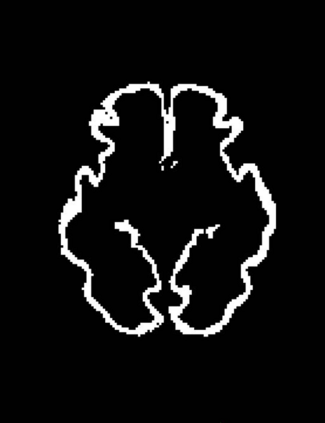

Fetal cortical plate segmentation is essential in quantitative analysis of fetal brain maturation and cortical folding. Manual segmentation of the cortical plate, or manual refinement of automatic segmentations is tedious and time-consuming. Automatic segmentation of the cortical plate, on the other hand, is challenged by the relatively low resolution of the reconstructed fetal brain MRI scans compared to the thin structure of the cortical plate, partial voluming, and the wide range of variations in the morphology of the cortical plate as the brain matures during gestation. To reduce the burden of manual refinement of segmentations, we have developed a new and powerful deep learning segmentation method. Our method exploits new deep attentive modules with mixed kernel convolutions within a fully convolutional neural network architecture that utilizes deep supervision and residual connections. We evaluated our method quantitatively based on several performance measures and expert evaluations. Results show that our method outperforms several state-of-the-art deep models for segmentation, as well as a state-of-the-art multi-atlas segmentation technique. We achieved average Dice similarity coefficient of 0.87, average Hausdorff distance of 0.96 mm, and average symmetric surface difference of 0.28 mm on reconstructed fetal brain MRI scans of fetuses scanned in the gestational age range of 16 to 39 weeks. With a computation time of less than 1 minute per fetal brain, our method can facilitate and accelerate large-scale studies on normal and altered fetal brain cortical maturation and folding.